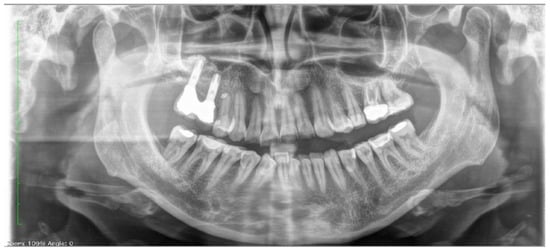

| Before | After | |

|---|---|---|

| Disharmonious smile | Yes | No |

| Dyschromia, dysmorphia, abrasions, and erosions of teeth | Yes | No |

| Anterior crowding in the upper arch | Yes | No |

| Anterior crowding in the lower arch | Yes | No |

| Upper transverse discrepancy | Yes | No |

| Presence of buccal corridors or black tunnels | Yes | No |

| Curve of Spee alteration | Yes | No |

| Curve of Wilson alteration | Yes | No |

| Functional movements with altered guides | Yes | No |

| Pain and/or noise ATM | Yes | No |